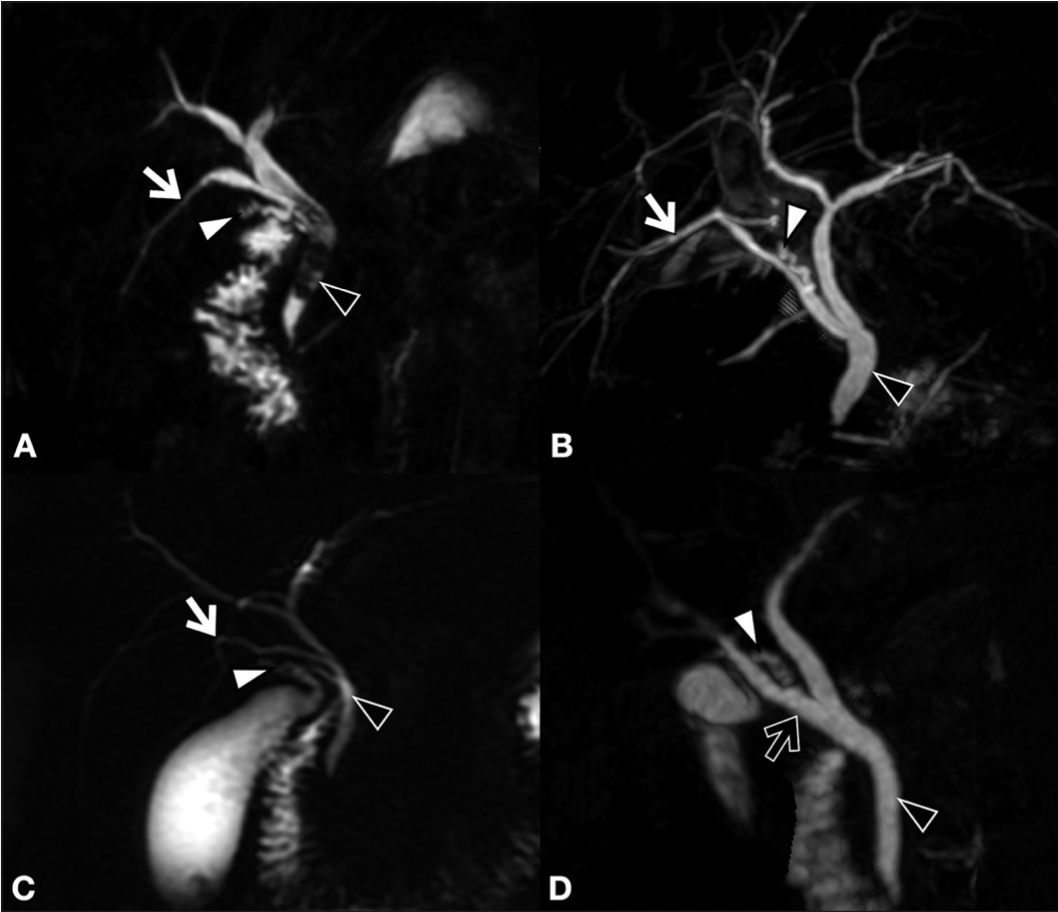

Patricia Díaz Ríos, Mohamed Hassin Mohamed Chairi, Marta Santidrián Zurbano

|

|